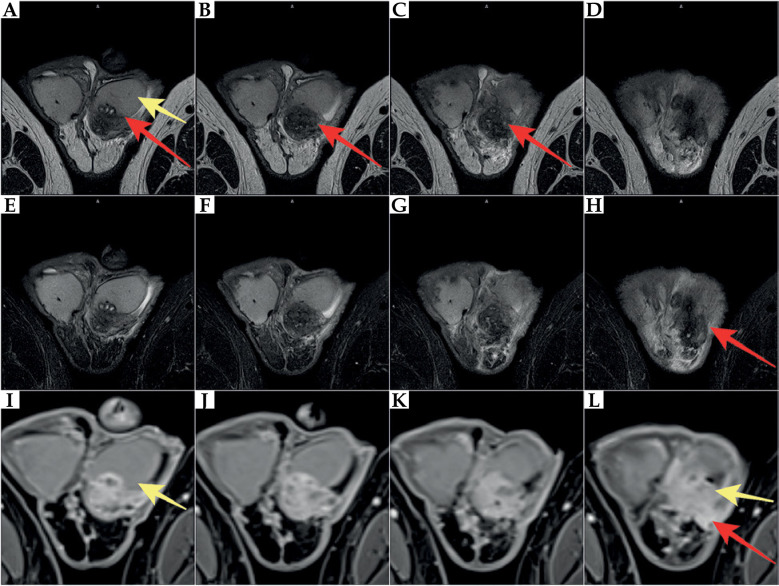

本文的目的是报道一例前列腺癌近距离放射治疗(BT)患者罕见的睾丸附睾炎并发症,该患者在BT治疗4周后行经输尿管前列腺切除术(TURP)。一位73岁的前列腺癌患者(中危组)符合高剂量率(HDR) BT联合雄激素剥夺治疗(ADT) 6个月(leuprorelin)的条件。由于BT术后尿潴留等症状加重,患者需要导尿。此外,下尿路和前列腺存在细菌性炎症。由于排尿障碍延长,行TURP,在BT完成4个月和TURP后拔管3个月后导致慢性睾丸附睾炎。由于长期炎症,治疗无效,切除左睾丸及左附睾。不幸的是,术后在床和左腹股沟出现炎症症状。由于这些不同程度的症状持续存在,因此引入了抗炎药和镇痛药。在HDR-BT后进行TURP过快可能会导致严重的并发症。对于接受BT治疗的患者,应慎用TURP,在BT后发生泌尿系统疾病时,必须采取保守和药物治疗,任何干预(TURP)应在BT后至少3-6个月进行,这一点尤其重要,因为随着时间的推移,辐射效应会逐渐发展。

The aim of this paper was to present a rare complication of orchiepididymitis in a patient treated with brachytherapy (BT) for prostate cancer, who underwent trans-ureteral resection of the prostate (TURP) four weeks after BT. A 73-year-old patient with prostate cancer (intermediate-risk group) was eligible for high-dose-rate (HDR) BT combined with androgen deprivation therapy (ADT) for 6 months (leuprorelin). Due to increased symptoms, such as urinary retention after BT, the patient required catheterization. Additionally, bacterial inflammation in the lower urinary tract and prostate was present. Due to prolonged micturition disorders, TURP was performed, leading to chronic orchiepididymitis four months after completion of BT and three months after catheter removal following TURP. Due to long-term inflammation, which was resistant to treatment, the left testicle with left epididymis was removed. Unfortunately, inflammatory symptoms occurred post-operatively in the bed and the left groin. Since these symptoms of varying severity continued, anti-inflammatory drugs and analgesics were introduced. TURP performed too quickly after HDR-BT might cause severe complications. Extreme caution regarding TURP should be exercised in patients undergoing BT. Conservative and pharmacological treatment must be introduced in the occurrence of urinary disorders after BT, and any intervention (TURP) should be performed at least 3-6 months after BT. This is especially crucial because of the development of radiation effect over time.